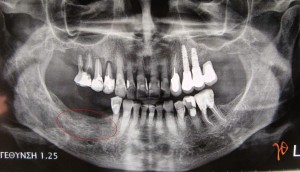

Η ασθενής παρέμεινε ασυμπτωματική και μετά από 8 μήνες, σε νέα πανοραμική ακτινογραφία, παρατηρήθηκε, στην ίδια περιοχή, η αποκατάσταση της φυσιολογικής δοκίδωσης του οστού της κάτω γνάθου(Εικόνα 3). Η ασθενής με δική της επιλογή είχε πλέον διακόψει την δενοσουμάμπη συνολικά για περίπου ένα χρόνο και αποφάσισε να προχωρήσει σε επανατοποθέτηση των οδοντικών εμφυτευμάτων.